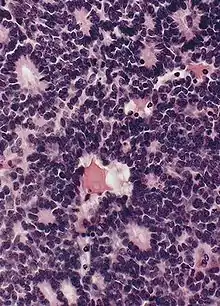

![]() | Diffuse B-cell lymphoma | Lymph node FNA specimen showing diffuse large B cell lymphoma. | Category: Histopathology of diffuse large B cell lymphoma | Diffuse large B-cell lymphoma |